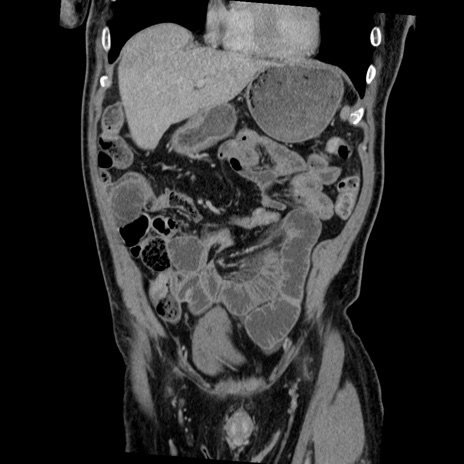

症例22(冠状断像)

【症例】50歳代男性

【主訴】腹痛

【現病歴】AVMからの被殻出血のため回復期リハ病棟入院中。 本日午後3時頃急に下腹部痛が出現した。

【既往歴】AVM、被殻出血、虫垂炎、高血圧

【身体所見】意識晴明、左半身不全麻痺、会話の理解は良好、36.5°C、腹部:膨隆、全体に板状硬、下腹部正中に圧痛点あり、反跳痛-、筋性防御不明、右下腹部にope scar

【データ】WBC 9400、CRP 0.06